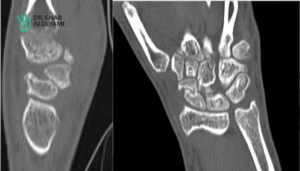

How is Acute Scaphoid Fracture Diagnosed?

The diagnosis of an acute scaphoid fracture typically involves:

- Standard X-rays are often the first-line imaging modality. However, occasionally acute scaphoid fractures X-ray may be deceiving, especially if the fracture is small.

- Advanced imaging studies like MRI or CT scans.

Prompt and accurate diagnosis is crucial in the case of scaphoid fractures to initiate appropriate treatment and minimise the risk of complications. If there is a suspicion of a scaphoid fracture, individuals should seek medical attention for a thorough evaluation.